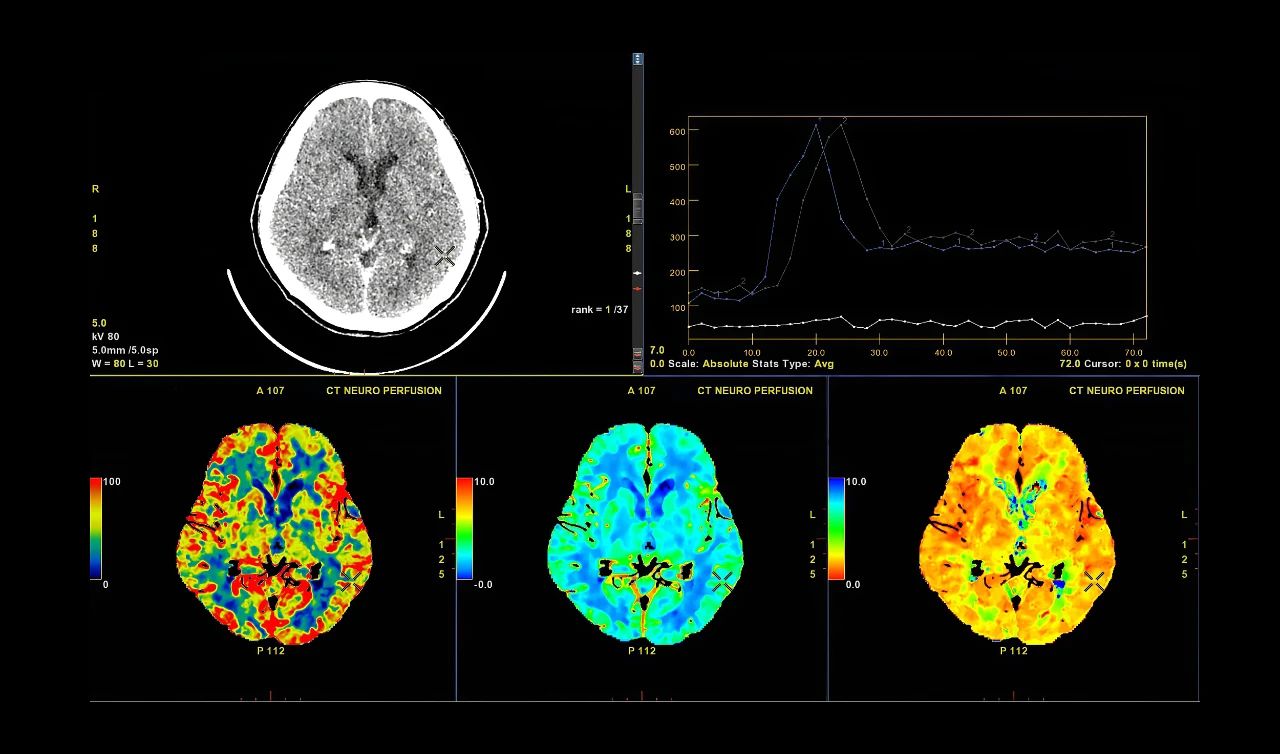

图片来源:文献1